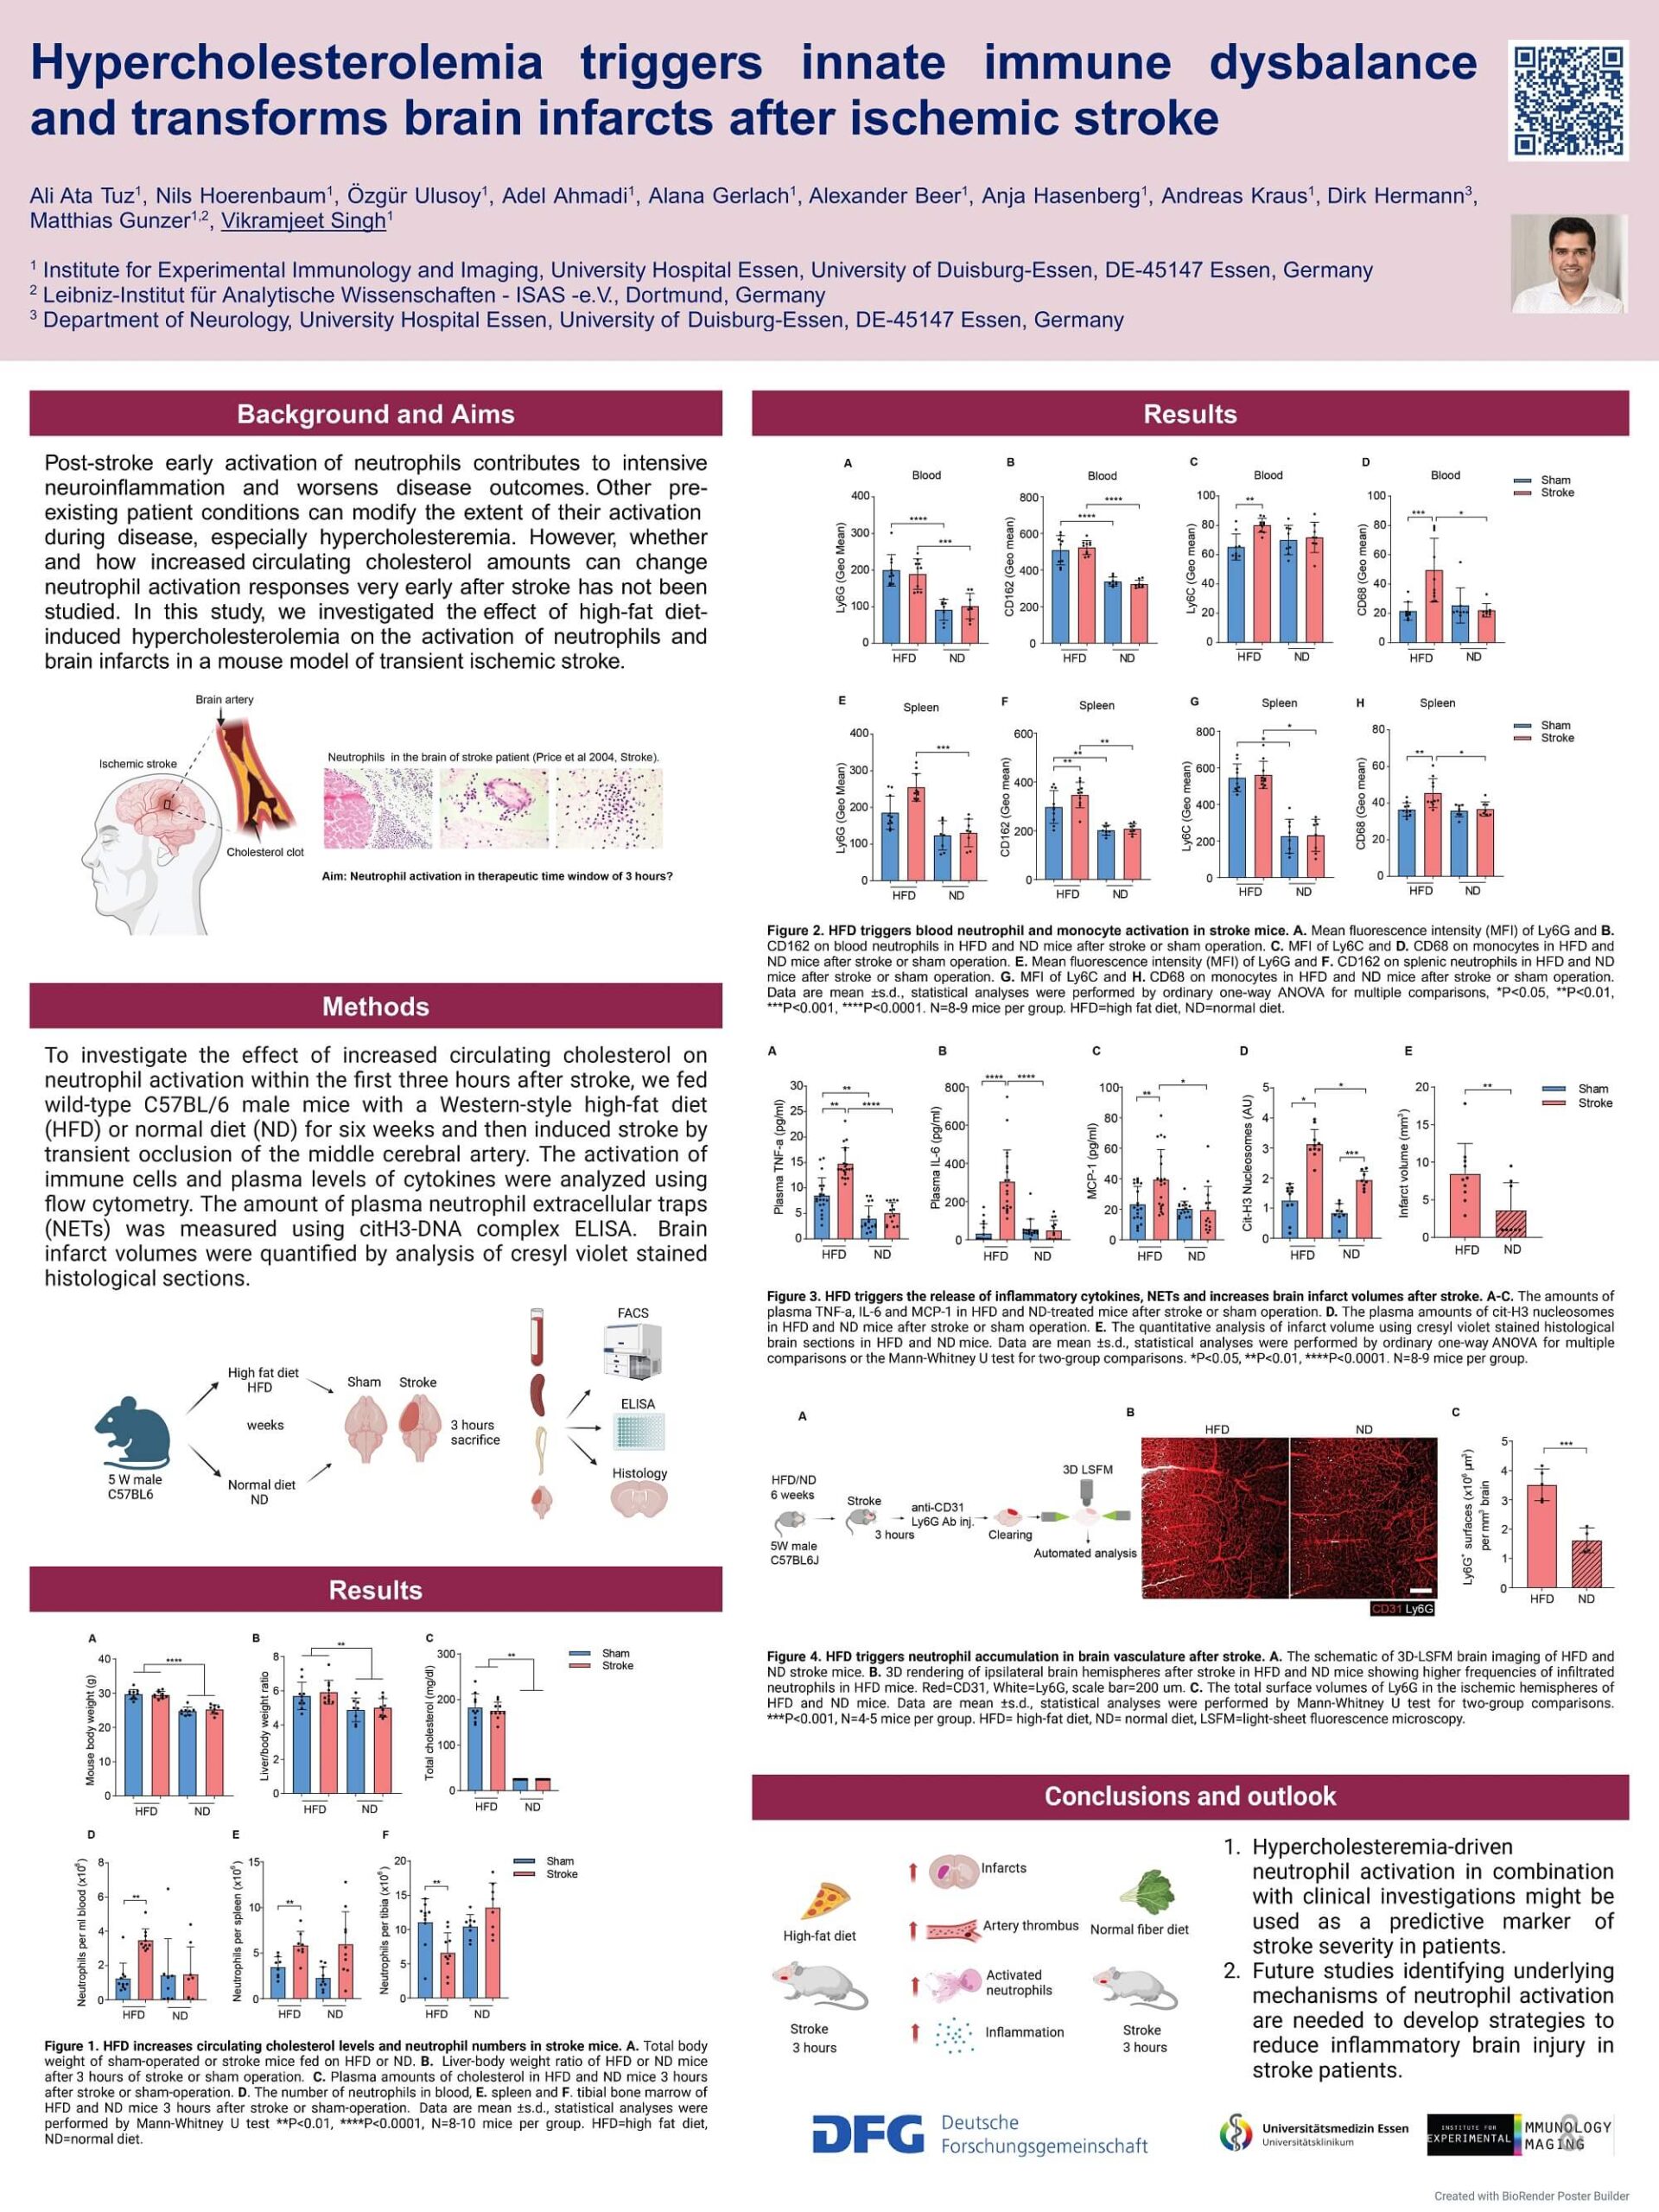

2. Tuz A, Hoerenbaum N, Ulusoy Ö, Ahmadi A, Gerlach A, Beer A, Kraus A, Hasenberg A, Hagemann N, Hermann D, Gunzer M, Singh V. Hypercholesterolemia triggers innate immune dysbalance and transforms brain infarcts after ischemic stroke. Frontier Immunology, 2025 Jan. With DFG funding

1. Nils Hörenbaum, University Duisburg-Essen (M.Sc. 2025), “Impact of high-fat diet on neutrophil activation and brain infarcts within three hours after ischemic stroke”.